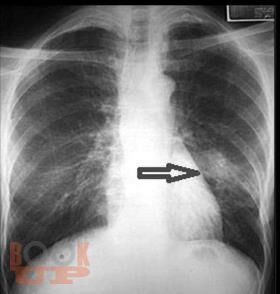

Излагается современная информация по классификации пневмонии у детей, ее эпидемиологии, этиологии, клинических особенностях в зависимости от этиологических и анатомо-физиологических факторов и фоновых заболеваний. Значительная часть пособия посвящена диагностике, принципам современной антибактериальной терапии с последних достижений в педиатрии.